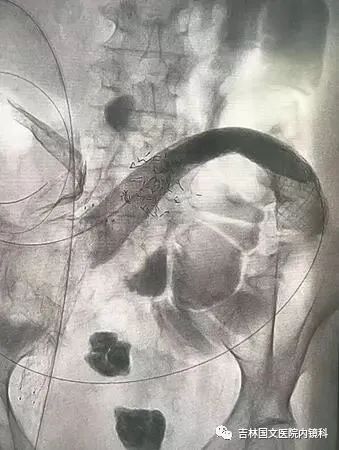

患者為結(jié)腸腫瘤致腸梗阻的病人,通過(guò)放置支架解除患者痛苦。手術(shù)開(kāi)始,先置入導(dǎo)絲與導(dǎo)管,注入造影劑,顯示腸管走形,以確定狹窄段長(zhǎng)度及部位,見(jiàn)乙狀結(jié)腸狹窄,造影劑可通過(guò),但導(dǎo)絲至結(jié)腸狹窄處通過(guò)失敗,候主任決定聯(lián)合內(nèi)鏡,進(jìn)行多學(xué)科合作。

邢主任迅速到達(dá),循腔進(jìn)鏡至乙狀結(jié)腸腫瘤處,見(jiàn)腫瘤環(huán)形生長(zhǎng),腫瘤似豆腐渣樣脆弱又霸道的侵占著本來(lái)就不寬敞的路,中指一樣粗細(xì)的腸鏡是無(wú)法通過(guò)了,只能做一盞指路的明燈,帶領(lǐng)導(dǎo)絲駛?cè)肽康牡兀谛现魅胃挥薪?jīng)驗(yàn)的操作以及候主任隨機(jī)應(yīng)變地配合下,整個(gè)操作行云流水,導(dǎo)絲終于順利通過(guò),送檢病理后,退出腸鏡。

又經(jīng)過(guò)一系列操作,腸道支架順利置入,患者術(shù)后排出大量稀便及氣體,腹脹明顯緩解,解決了患者的生理難題,提高了生活質(zhì)量。